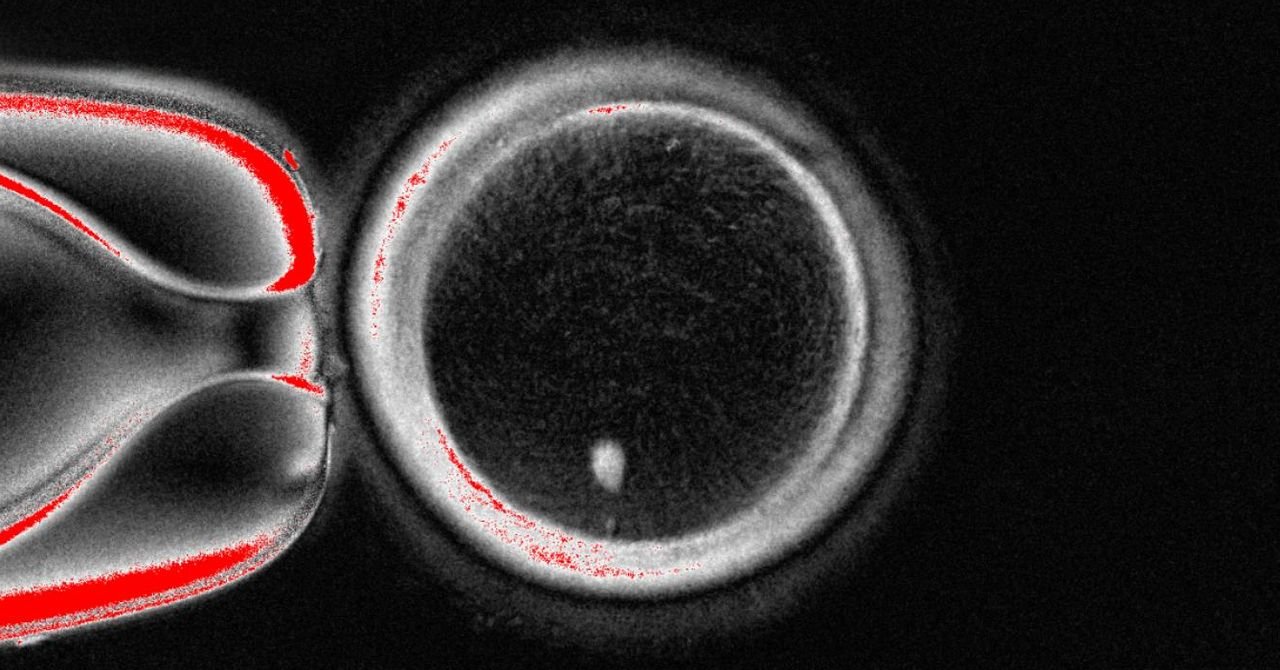

Mitinori Saitu at Kyoto University first how his team enrolled in 2018 Human blood cells have turned into stem cellsWhich they were then transformed into human eggs, but they were very immovable to be fertilized to make fetuses.

“Their method is very sophisticated and well -integrated,” but due to the high rate of chromosomal defects, “the clinical application is very inefficient and high risk to immediately apply,” said Hayasi Oregon Group, a professor at Osaka University.

“The technology of mitomiosis is an important technical innovation and can be extremely valuable for our understanding of myosis in human eggs,” Clark says.